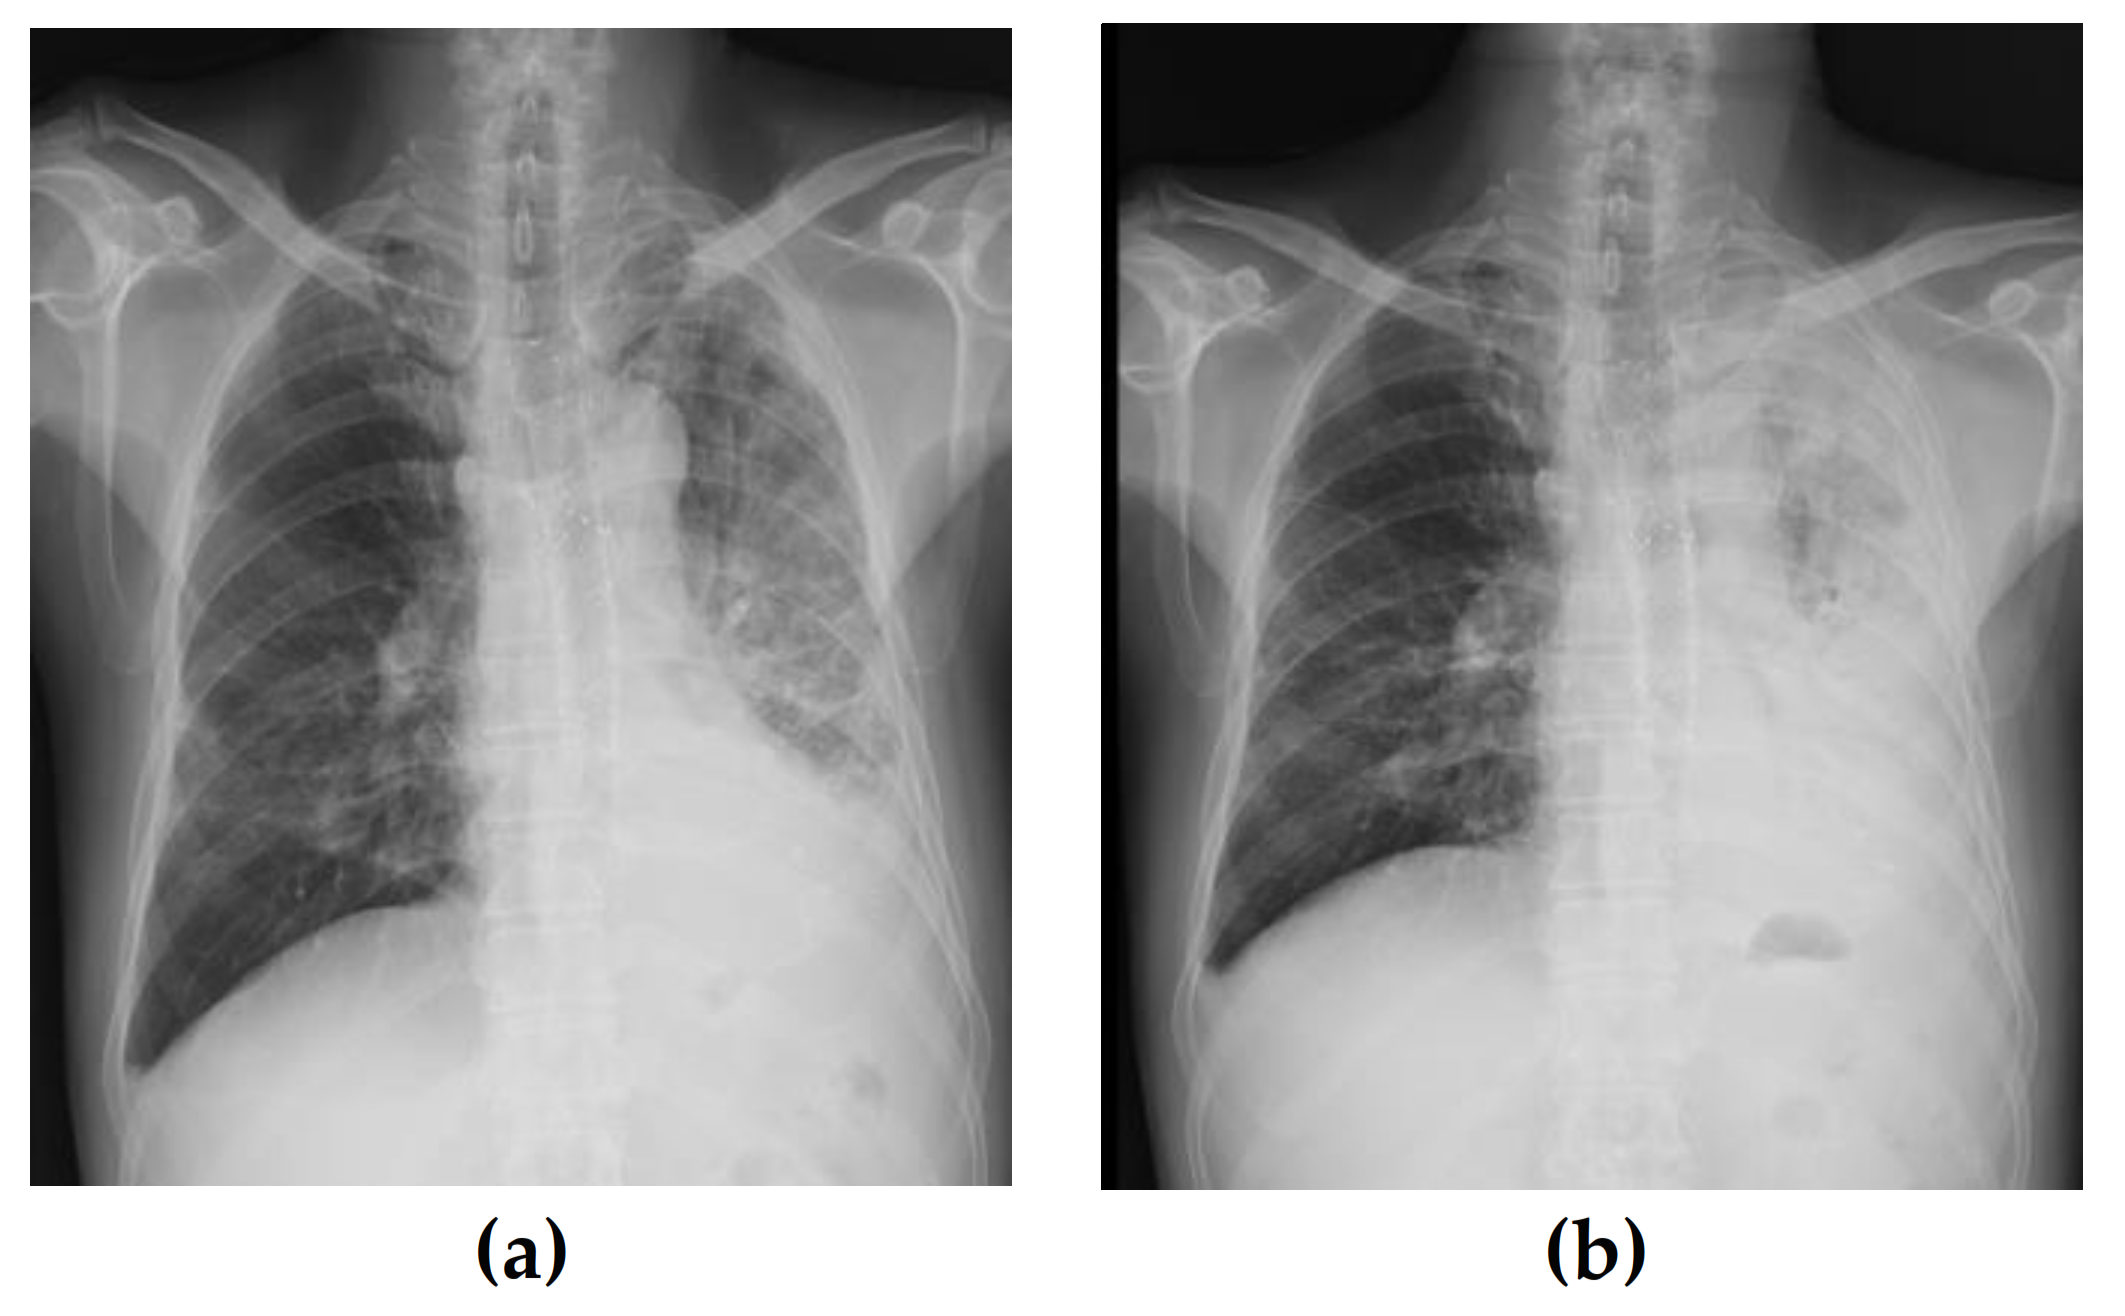

2. Case Report